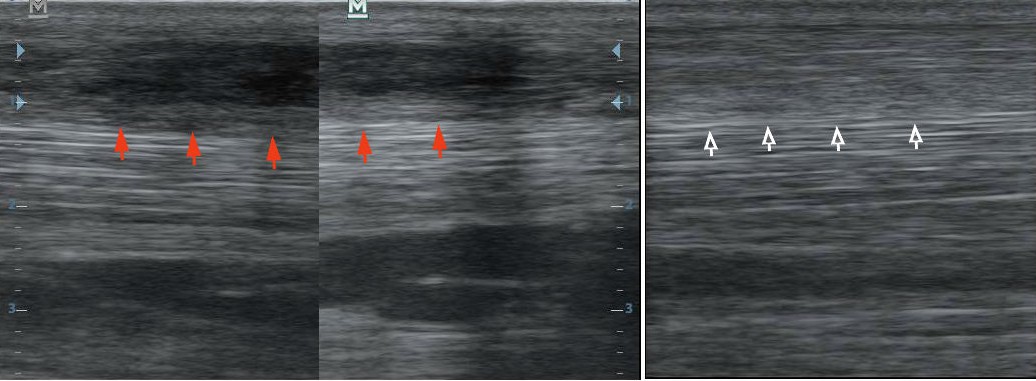

A bal oldali képen egy friss, felületes ujjhajlító ín sérülés látható. A középső képen bejelölve a sérülés, ami 33%-os, kifejezetten nagy defekt. A jobb oldali képen két hónappal az őssejt beadás után a sérülés egyáltalán nem látható!

Az előző eset hosszmetszetben. A piros nyilak felett a friss sérülés a bal oldali képen. A jobb oldali képen a fehér nyilak felett a teljesen kitöltődő defekt és majdnem tökéletes szerkezetű ín.